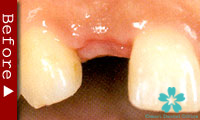

歯を一本だけ失った場合

“失われた1本の歯根の代理品”としてインプラントを1本だけ使って失った歯の部分を修復する方法は、最も洗練された治療方法であり、審美的にも満足のいく結果が得られます。

1本のインプラントによってあたかも自分の天然歯のように自然に感じられます。顎骨の”萎縮”の心配もなく、本来の骨量を維持できます。

ブリッジを入れる時のように、健康な隣の歯を削る必要がありません。